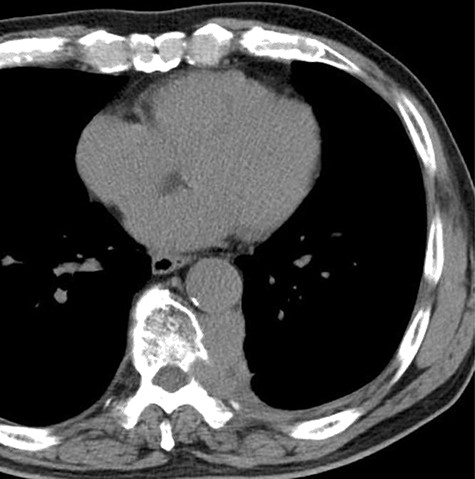

Since the disease progression might cause paresis, paralysis and loss of bowel/bladder function, palliative thoracic radiotherapy was planned. He received 36 Gray palliative radiotherapy. Six weeks after radiotherapy, the tumor was effectively decreased in size (Fig. 4).

The computed tomographic findings after 6 weeks after radiotherapy.